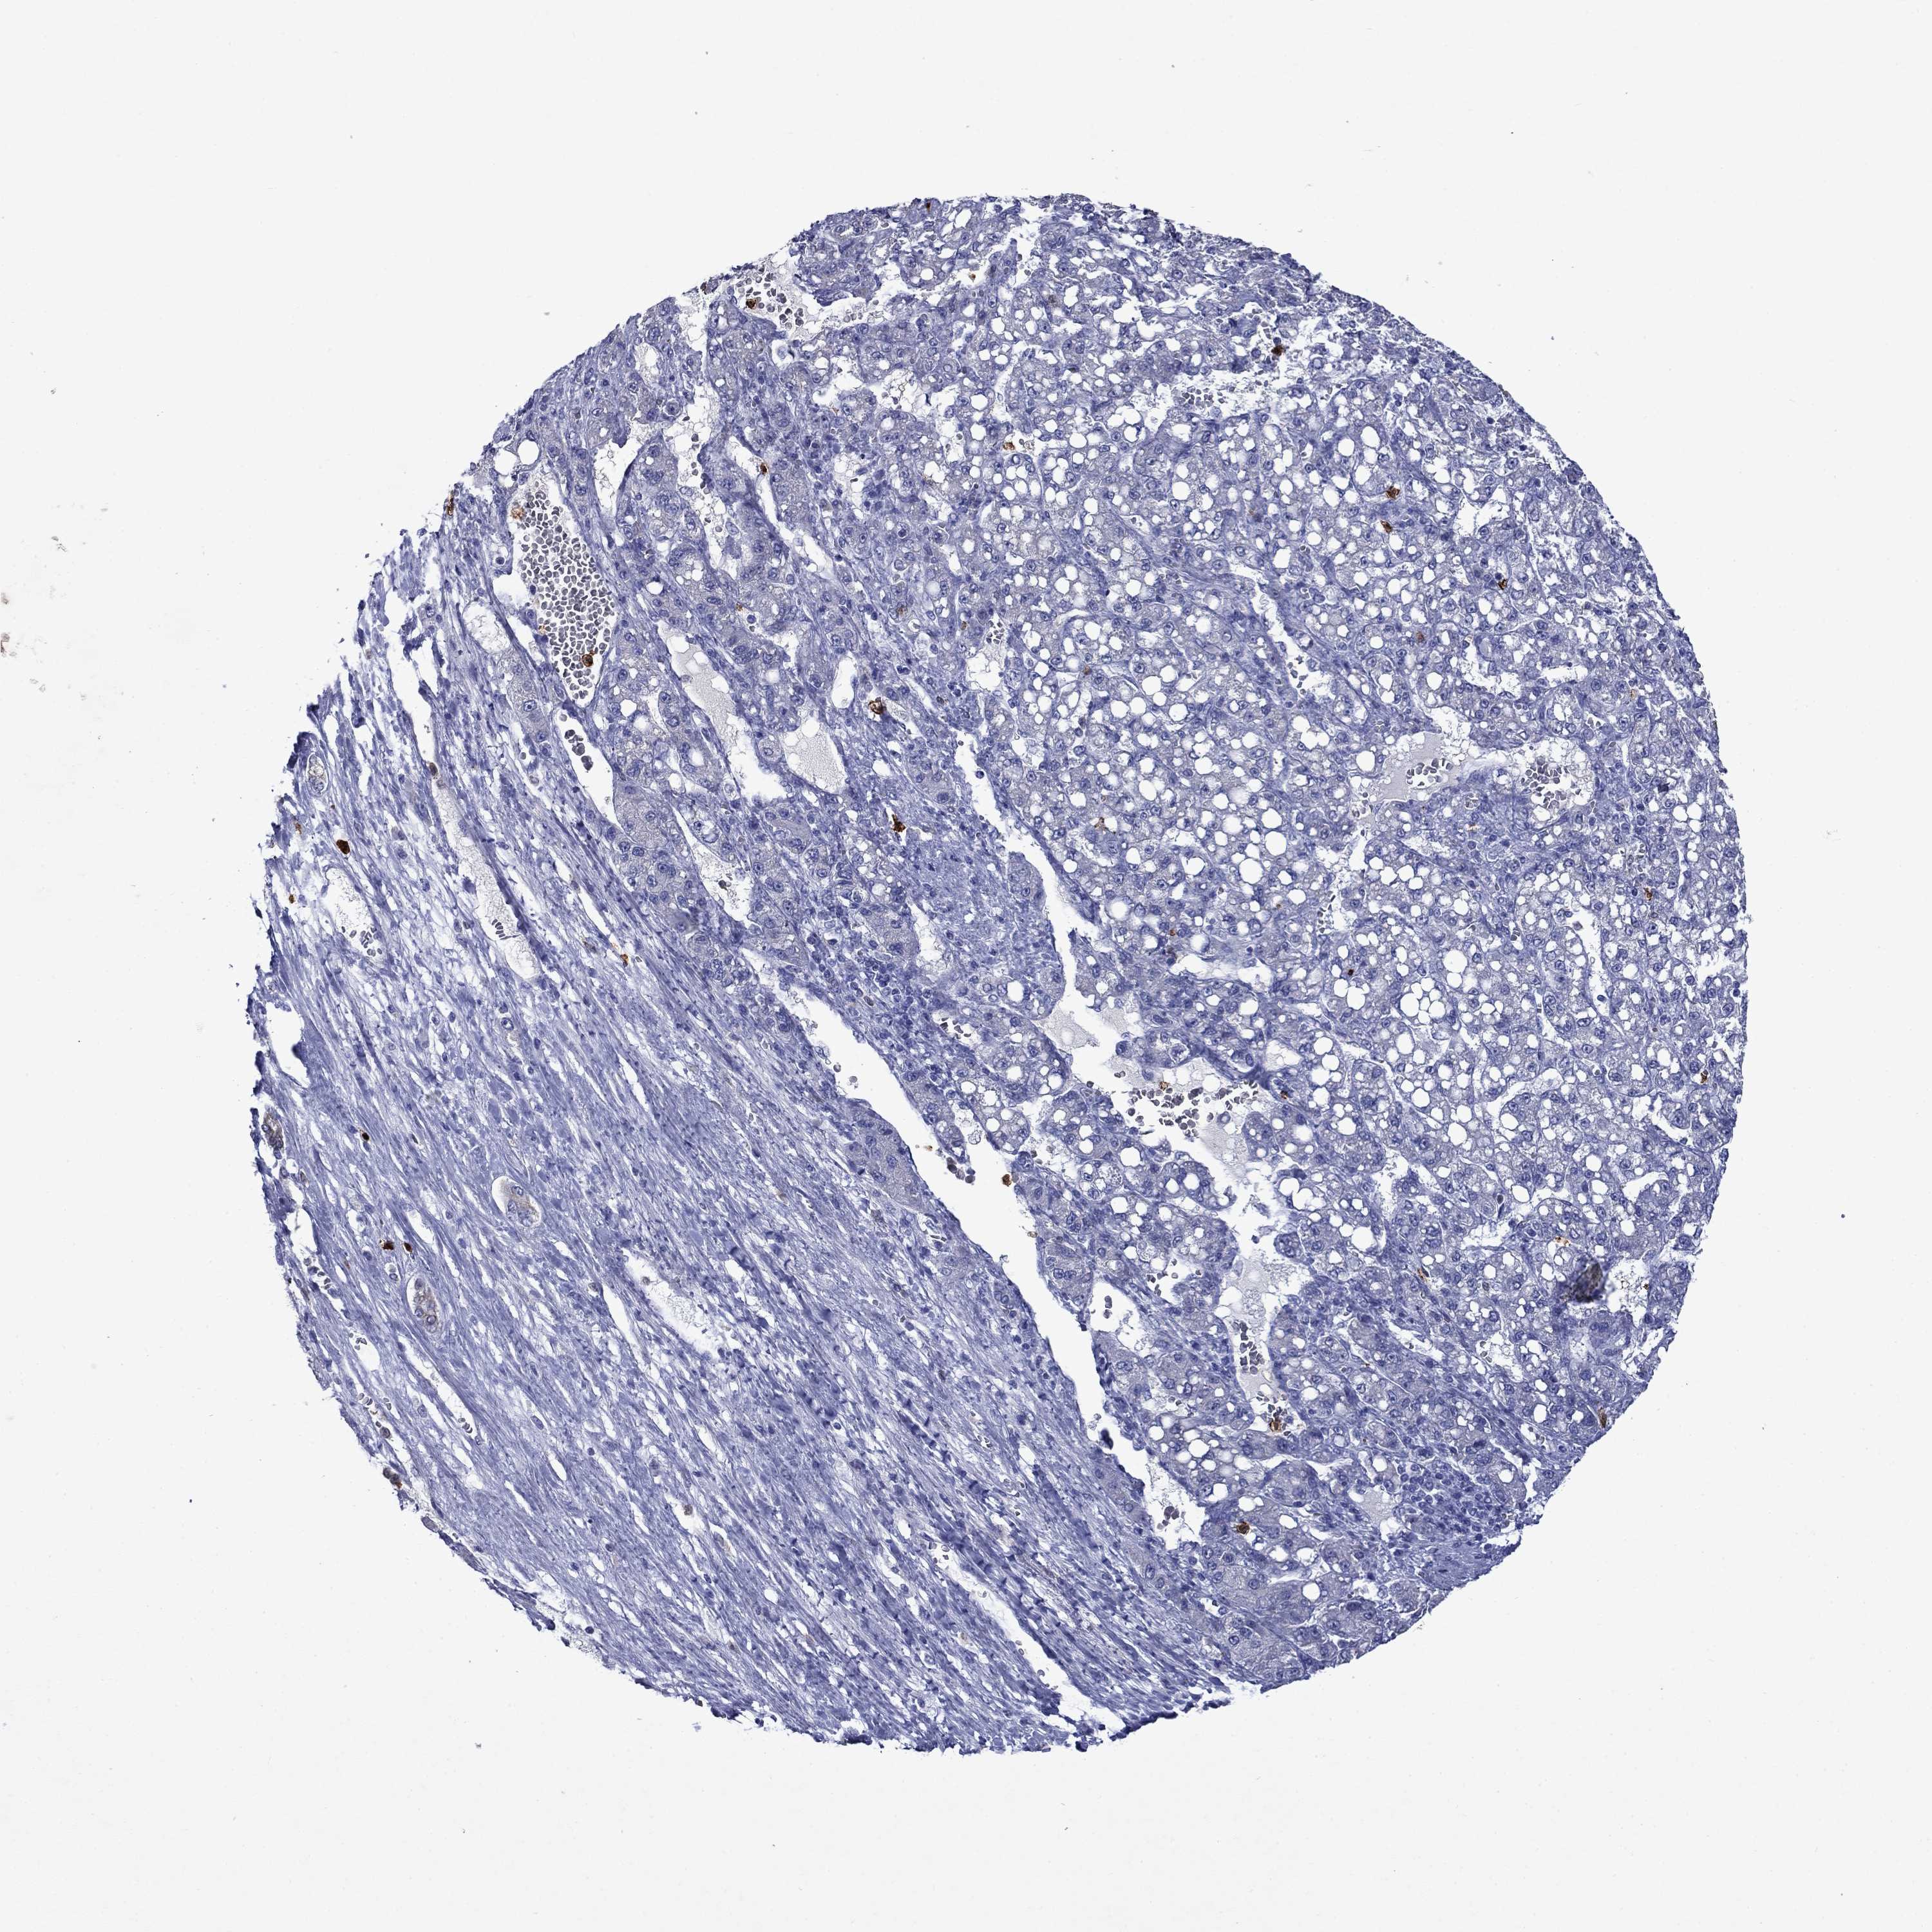

LIVER CANCER - Protein expressioni

A mouse-over function shows sample information and annotation data. Click on an image to view it in a full screen mode. Samples can be filtered based on level of antibody staining by selecting one or several of the following categories: high, medium, low and not detected. The assay and annotation is described here.

Antibody stainingi

Antibody staining in the annotated cell types in the current human tissue is reported as not detected, low, medium, or high, based on conventional immunohistochemistry profiling in selected tissues. This score is based on the combination of the staining intensity and fraction of stained cells.

Each image is clickable and will lead to virtual microscopy that enables deeper exploration of all samples and also displays staining intensity scores, fraction scores and subcellular localization as well as patient and tissue information for each sample.

Antibody HPA046700

Antibody HPA076024

Staining

High

Medium

Low

Not detected

Intensity

Strong

Moderate

Weak

Negative

Quantity

>75%

75%-25%

<25%

None

Location

Nuclear

Cytoplasmic/membranous

Cytoplasmic/membranous,nuclear

Cholangiocarcinoma

Carcinoma, Hepatocellular, NOS